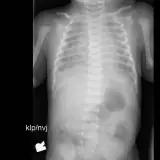

Over 2,100 interactive radiology cases, curated by radiologists for your level of training. Scroll, window, and view cases full screen — just like on PACS. Click linked findings in each writeup to jump straight to them on the image. Cases include sample reports, a focused discussion section, original illustrations, and videos.

完全交互式病例,配备您在 PACS 上期待的各项工具——滚动、调窗、缩放、平移、测量、ROI 和全屏模式。

丰富的标注直接在病例图像上突出关键发现。点击病例讲解中的关联发现,即可跳转至其在扫描上的精确位置。